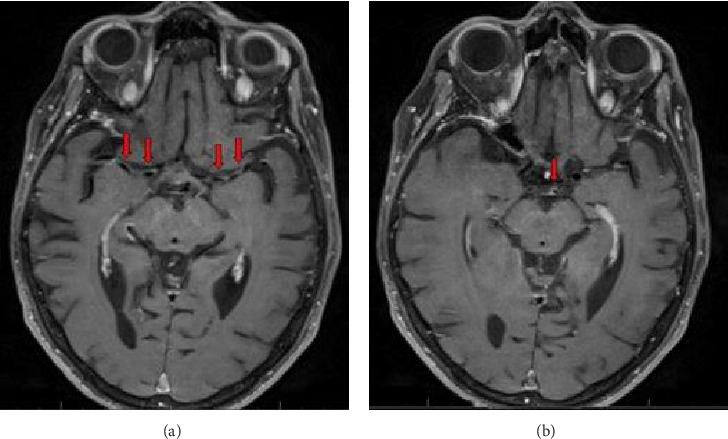

Giant cell arteritis (GCA) is an inflammatory vasculitis affecting large and medium-sized arteries, leading to complications such as arterial dissection, blindness, and stroke. Rarely, GCA presents with Horner's syndrome due to sympathetic neuron involvement from arterial inflammation. This case report discusses an 82-year-old female with hypertension, atrial fibrillation, and arthritis who presented with a 24 h history of right eye ptosis, blurred vision, dizziness, and aching eye pain. She had a mild headache and tenderness over the right temporomandibular joint but no temporal artery tenderness. Examination revealed right eye ptosis and miosis, indicative of Horner's syndrome, with no other neurological deficits. Lab results showed elevated ESR (68 mm/h) and CRP (16 mg/L). MRI with contrast revealed mild to moderate stenosis and enhancement in bilateral MCAs and basilar artery with inflammation in the right distal extracranial ICA, suggesting an inflammatory process. The patient was started on prednisone 40 mg daily. A temporal artery biopsy confirmed GCA with characteristic histopathological findings. Her prednisone dosage was increased to 60 mg/day, and she was started on tocilizumab. This case underscores the need to consider GCA in patients with Horner's syndrome and the importance of vessel wall imaging, as early corticosteroid treatment can prevent complications like vision loss and stroke.